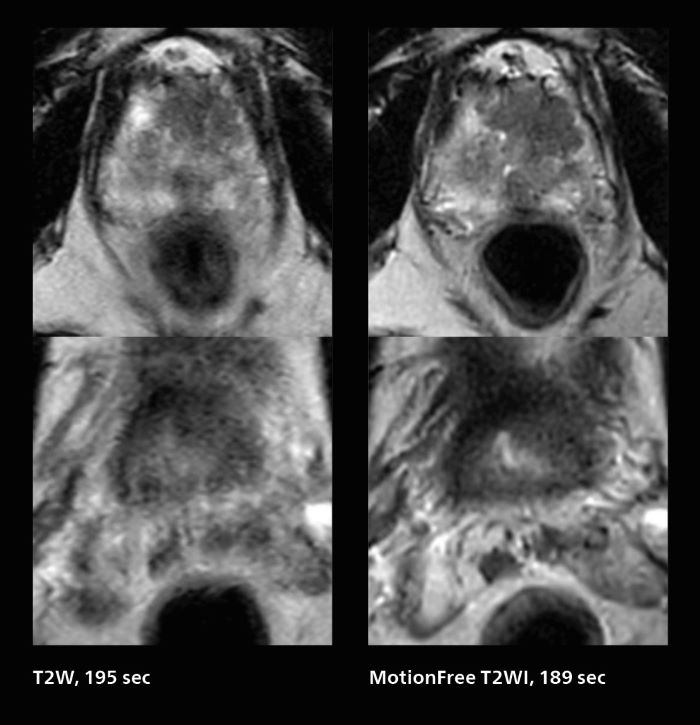

Prostate cancer MRI

MRI was performed in a patient with PSA 89.2. Evaluation of T2WI images was difficult due to rectal peristalsis. Using SmartSpeed MotionFree T2WI provided very good imaging quality. Seminal vesicle gland invasion is easily seen. Biopsy resulted in GS4+5=9. Performed on Elition X.